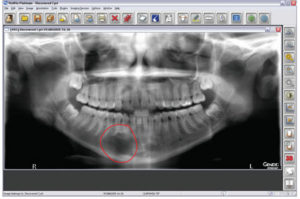

Besides aesthetics, the pan is also my first and foremost tool for general pathology. From the pan, I find lesions, supernumeraries, and situations that greatly decrease the morbidity and mortality of my patients. For example, a routine pan on a 17-year-old showed a 3-centimeter traumatic bone cyst that was not diagnosed from a set of intraoral X-rays. As a result, the patient had surgery, and was able to keep all of her teeth. If the cyst was not found and treated at that time, she could have experienced major loss of her mandible as well as teeth. Digital imaging technology has turned out to be life changing for me and for my patients.